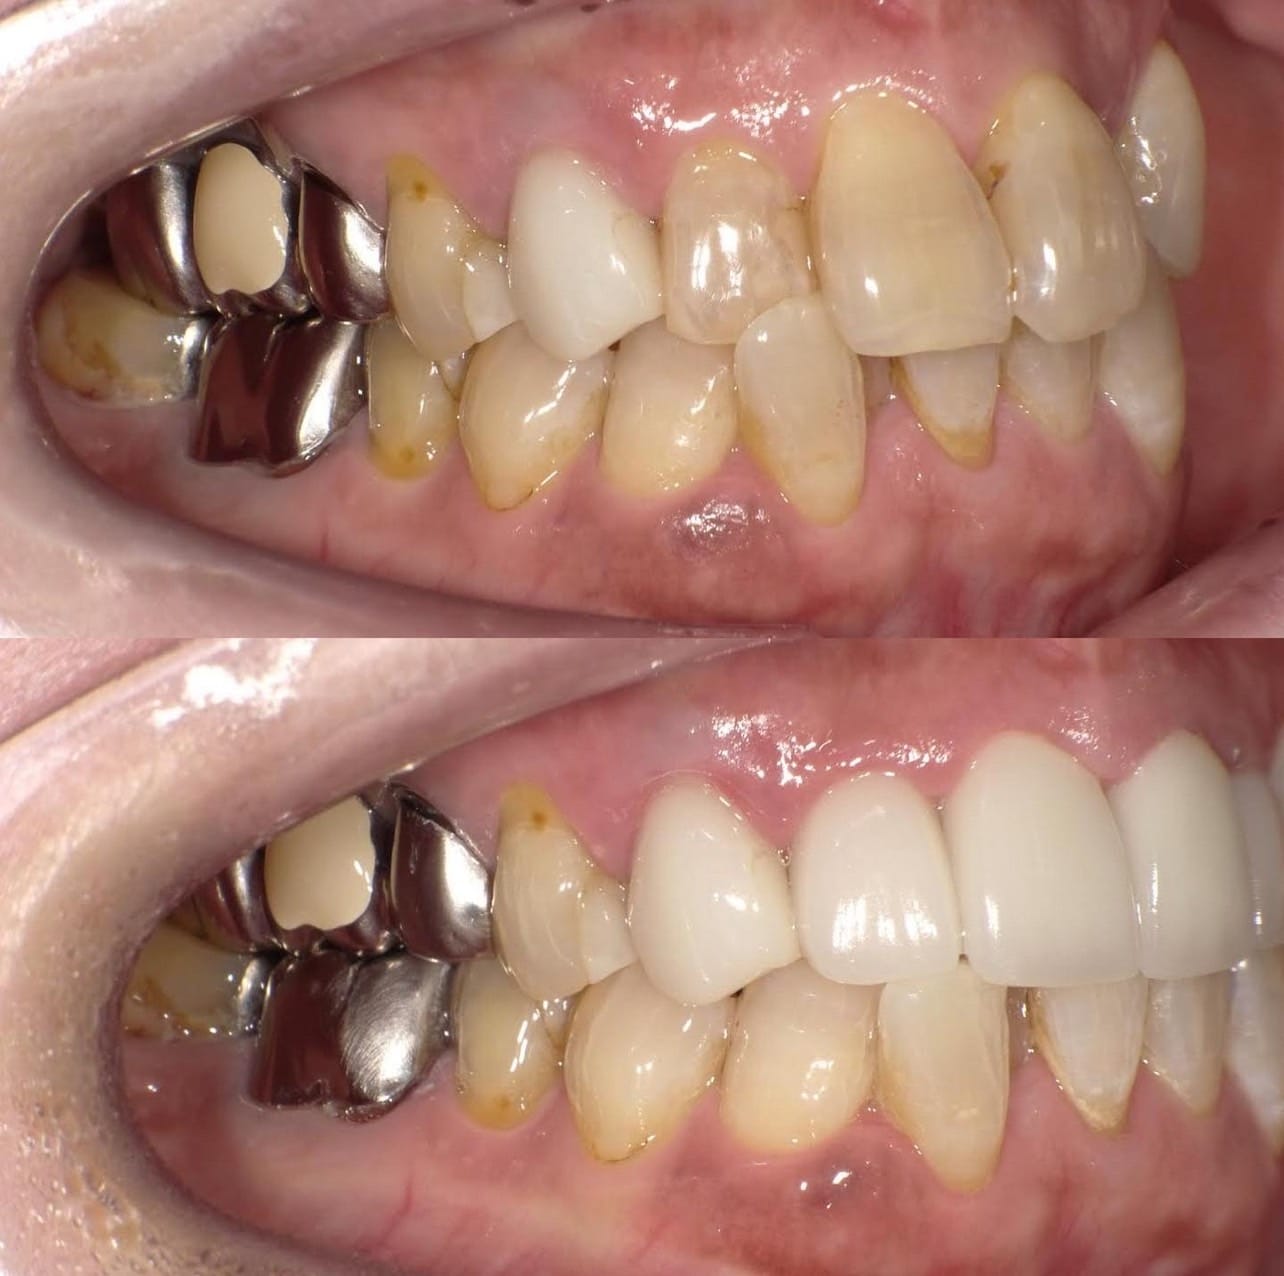

「ずっと放置してしまっていた。今回はちゃんとしっかり治したい」ということで、強い意志をもって来院してくださった患者様の症例です。

インプラント治療、セラミック治療、歯周病治療により、審美性と機能、咬みあわせの再建を行いました。

患者様は咬みあわせの確立により、食事もしやすく、普段の顎関節の状況も良くなり、機能の回復にも満足してくださり、また審美性も喜んでくださいました。

放置期間が長くだいぶ骨が溶けてしまっていたので、前歯部のインプラントは骨の再生療法などが必要だったりしましたが、患者様が治療への前向きな姿勢をだしてくださっていましたので期間も最短で終わりました。

一度放置してしまうと、億劫になってしまってなかなか行動に移すのは難しいと思いますが、少しでも早く治してあげた方が毎日の食事も楽になりますし、お顔の見栄えもお顔の骨格の歪みも改善します。

担当 理事長 佐藤 悠野